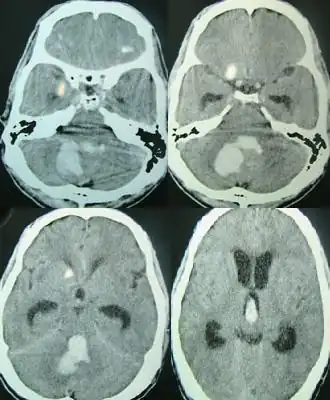

![]() Escaneado por la TC de una hemorragia cerebral espontánea encontrada en los ventrículos laterales. | ||

| Diagnóstico | Escaneo de Tomografía computarizada (TC)[1] | |